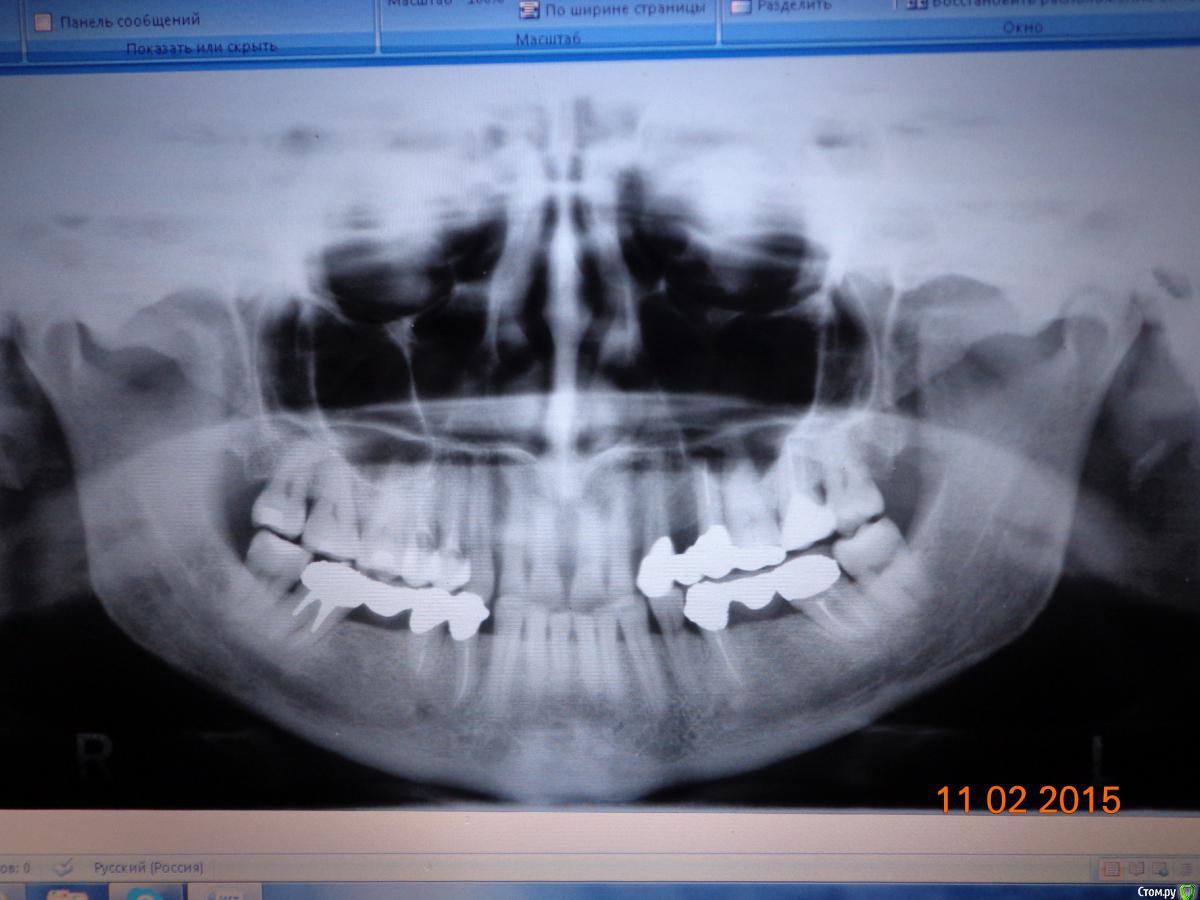

pharmaceut Опубликовано 11 февраля, 2015 Поделиться Опубликовано 11 февраля, 2015 Обращаюсь к профессионалам за помощью и советом. Протезировалась 8 лет назад, почти год, со всякими обследованиями и тп. Аллергия на металлы. Из образцов предоставленных в лабораторию подошел серебряно палладиевый сплав. Из него были выполненны коронки и облицованы керамо композитом. Все время преследовало ощущение нечищенных зубов, и присутствия пищи под мостами... Этим летом верхний левый мост слетел, клею его по сей день на корегу, у нижнего правого откололась часть последнего зуба. Пора сдаваться))) Побывала у нескольких врачей , предлагают разные варианты протезирования, определиться очень сложно, разброс цен ошеломляет. Я в растерянности, знакомых с похожей непереносимостью нет, спс больше не хотелось бы. Сдала анализ на переносимость Кобальт Хром ( хотелось недорогую металло керамику). В лаборатории сказали не подходит, и посоветовали тот же сплав, но из другой клиники попробовать. Снимок прилагаю, пишу немного сумбурно, волнуюсь. Ссылка на комментарий

pharmaceut Опубликовано 17 февраля, 2015 Автор Поделиться Опубликовано 17 февраля, 2015 Спасибо что ответили доктор. Вопросы все равно остаются. У меня стоис СП вкладка и штифт, они совместимы с титаном и цирконием, или их необходимо извлекать? Почему вы не предложили имплантировать верх? Там какие то проблемы? Снимок получился перевернутым, Слева два моста друг над другом, а справа один нижний. Если это важно, могу переснять и добавить. Ссылка на комментарий

SDC Опубликовано 18 февраля, 2015 Поделиться Опубликовано 18 февраля, 2015 Спасибо что ответили доктор. Вопросы все равно остаются. У меня стоис СП вкладка и штифт, они совместимы с титаном и цирконием, или их необходимо извлекать? Почему вы не предложили имплантировать верх? Там какие то проблемы? Снимок получился перевернутым, Слева два моста друг над другом, а справа один нижний. Если это важно, могу переснять и добавить.C диоксидом циркния совместим любой металлических сплав.По-поводу извлекать или нет: если имеются показания к ревизии корневых каналов, то извлекать автоматически.Если с каналами порядок - извлекать по причине осложненного аллергологического анамнеза (с Ваших слов об анализих из лаборатории)На в.ч. в области отсутствующего 25 зуба нет места для имплантата - 24 сместился назад. Ссылка на комментарий